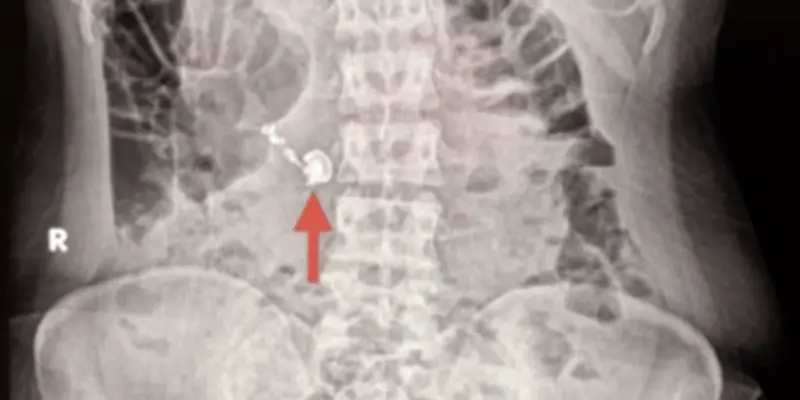

Après avoir réalisé son erreur, la femme a rapidement consulté des professionnels de santé. Les médecins ont procédé à des examens, confirmant la présence de l'écouteur dans son système digestif. Une procédure d'extraction a été nécessaire pour retirer l'objet, évitant ainsi des complications potentielles telles que des obstructions ou des lésions internes.